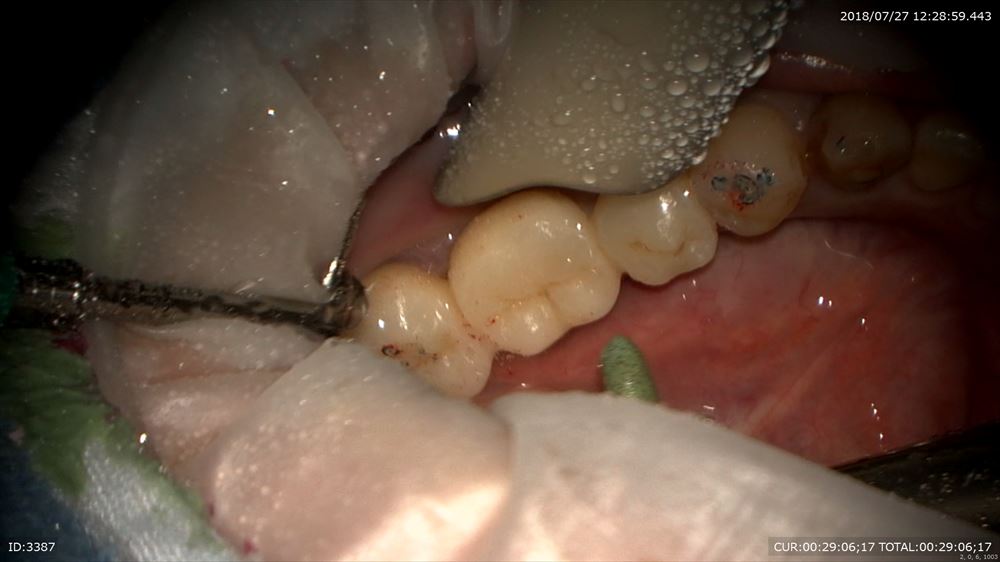

この様に仮歯で2ヶ月観察。問題なし。歯周病学会認定衛生士の歯周治療後私に昨日帰ってきました。

再発なしなので型とりへ

マイクロスコープを使用し準備

糸を入れるのは隙間を作るから。この緑を外すと

ここ。隙間ができここに型取りの材料を流します。